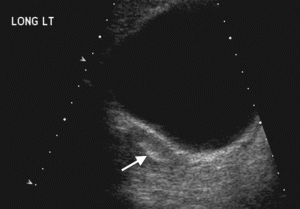

Picture 2 – Mullerian Agenesis Image

- Ultrasound